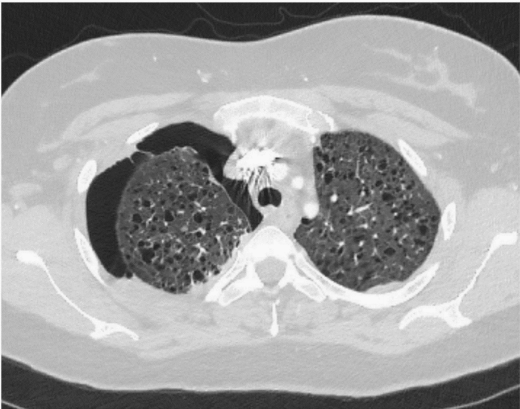

胸片显示右侧气胸,伴少量至中度积液(图1)。CT显示右侧大量气胸和同侧胸腔积液

图3 胸部轴位CT显示右侧胸腔积液伴双侧弥漫性囊肿和右侧少量胸腔积液。